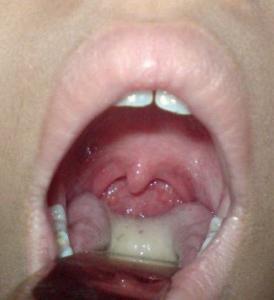

При обнаружении бактерий группы А в горле, дети постарше жалуются на першение, дискомфорт, боль. Миндалины набухают, присоединяется кашель, отек горла, поднимается температура, увеличиваются лимфатические узлы Если при гнойном процессе состояние ребенка ухудшается, возможно, это симптомы скарлатины. В этом случае появляется сыпь, язык обложен налетом, возникает рвота и понос.

Как правило, взрослые тяжело переносят гнойную ангину. Признаки болезни те же, что и у детей, но ярко выражены. Слизистая горла отечная, гиперемирована, гной в лакунах. Температура резко повышена. Присутствует слабость, усталовсть, головная боль. При распространении бактерий с током крови по организму возникает сепсис.

Стрептококк, находящийся в горле – служит причиной таких заболеваний, как тонзиллит, фарингит, скарлатина. Клинически характеризуется следующими признаками:

- першение и боль в горле при глотании;

- появление налета на языке и миндалинах;

- кашель;

- боль в груди;

- лихорадка;

- высыпания на коже и языке малинового оттенка – при скарлатине.